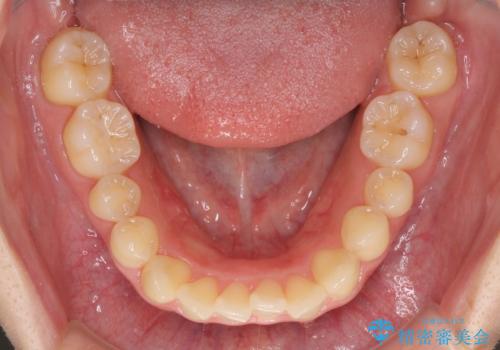

- 前歯のデコボコを気にして来院された患者様です。

上顎右側犬歯が八重歯になっており、それによって奥歯が前方に移動しているため、右側の咬み合わせの改善が必要と判断されました。